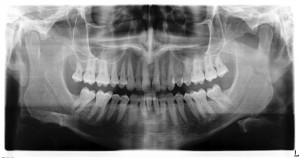

In our centre, we provide Biocompatible, Mercury-free Dentistry and Detoxification therapies for the whole family, Dental Implantology, IV-Chelation therapy, A.R.T., Family Constellation therapy and Sports Injury and Rehabilitation Massage therapy.